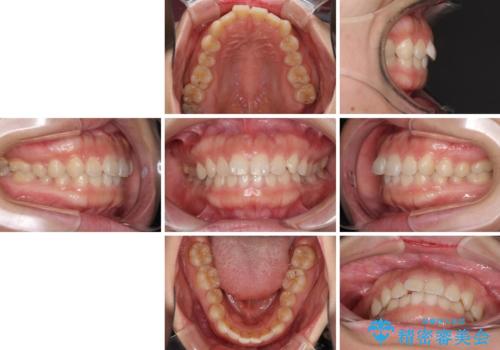

- 前歯のデコボコを治したいとのことで来院された患者様です。

上下顎ともに歯列全体の側方拡大とIPR(歯と歯の間を削る)によってデコボコが解消するように設計し、インビザラインにより治療を行うこととしました。

後方移動に際し、残っていた上顎の親知らずを抜歯することとしました。